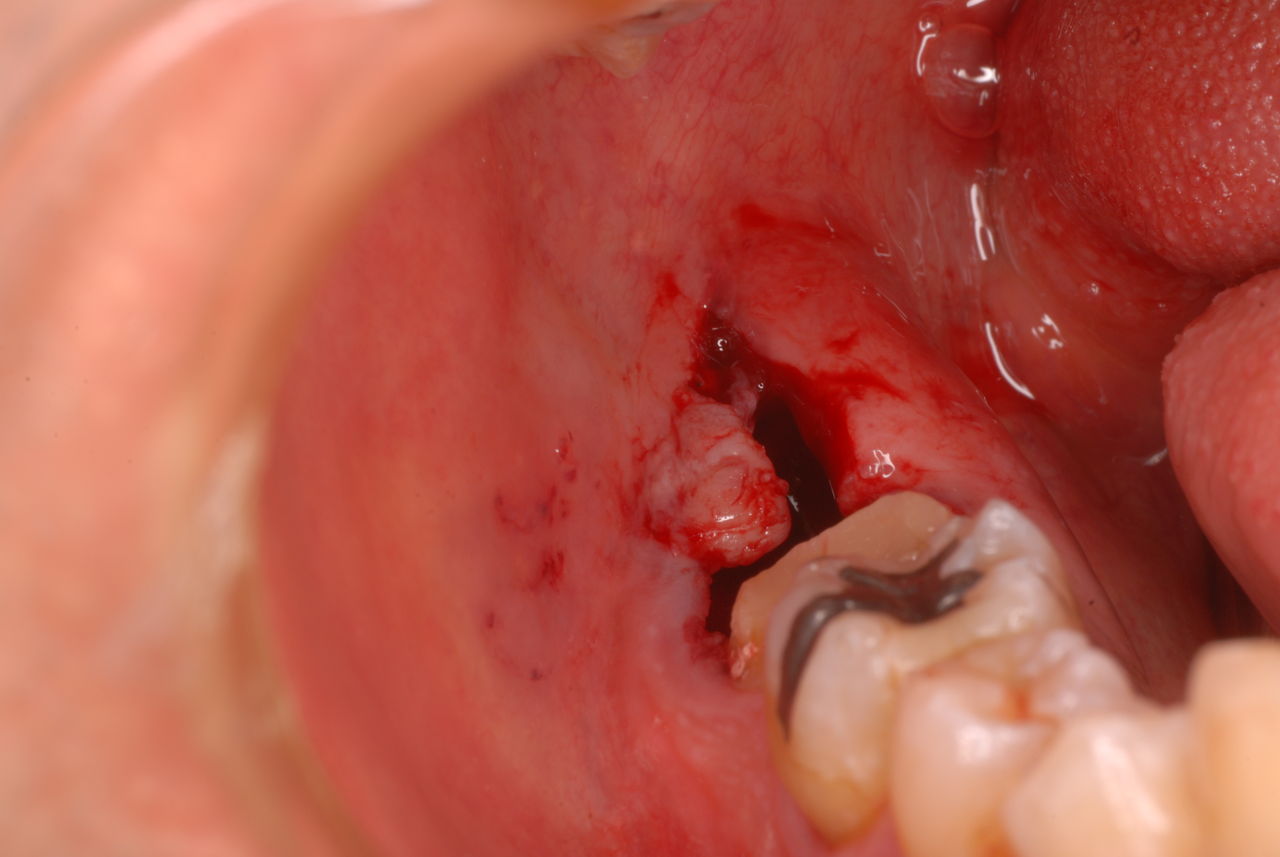

下記は患者に言われるままに血だらけでの不潔な状態で虫歯をとり埋めたようで全然適合していませんし、外れそうになっていました。

外したところです。中は虫歯のオンパレードでした。

適合が悪い銀歯が装着されていて更に虫歯の取残しにより歯髄炎症を起こして神経を取らざるをえなくなりました。神経を除去すれば痛みはなくなります。でもそれは死ぬことなのです。ほぼ寿命は半減したと考えるしかないのです。